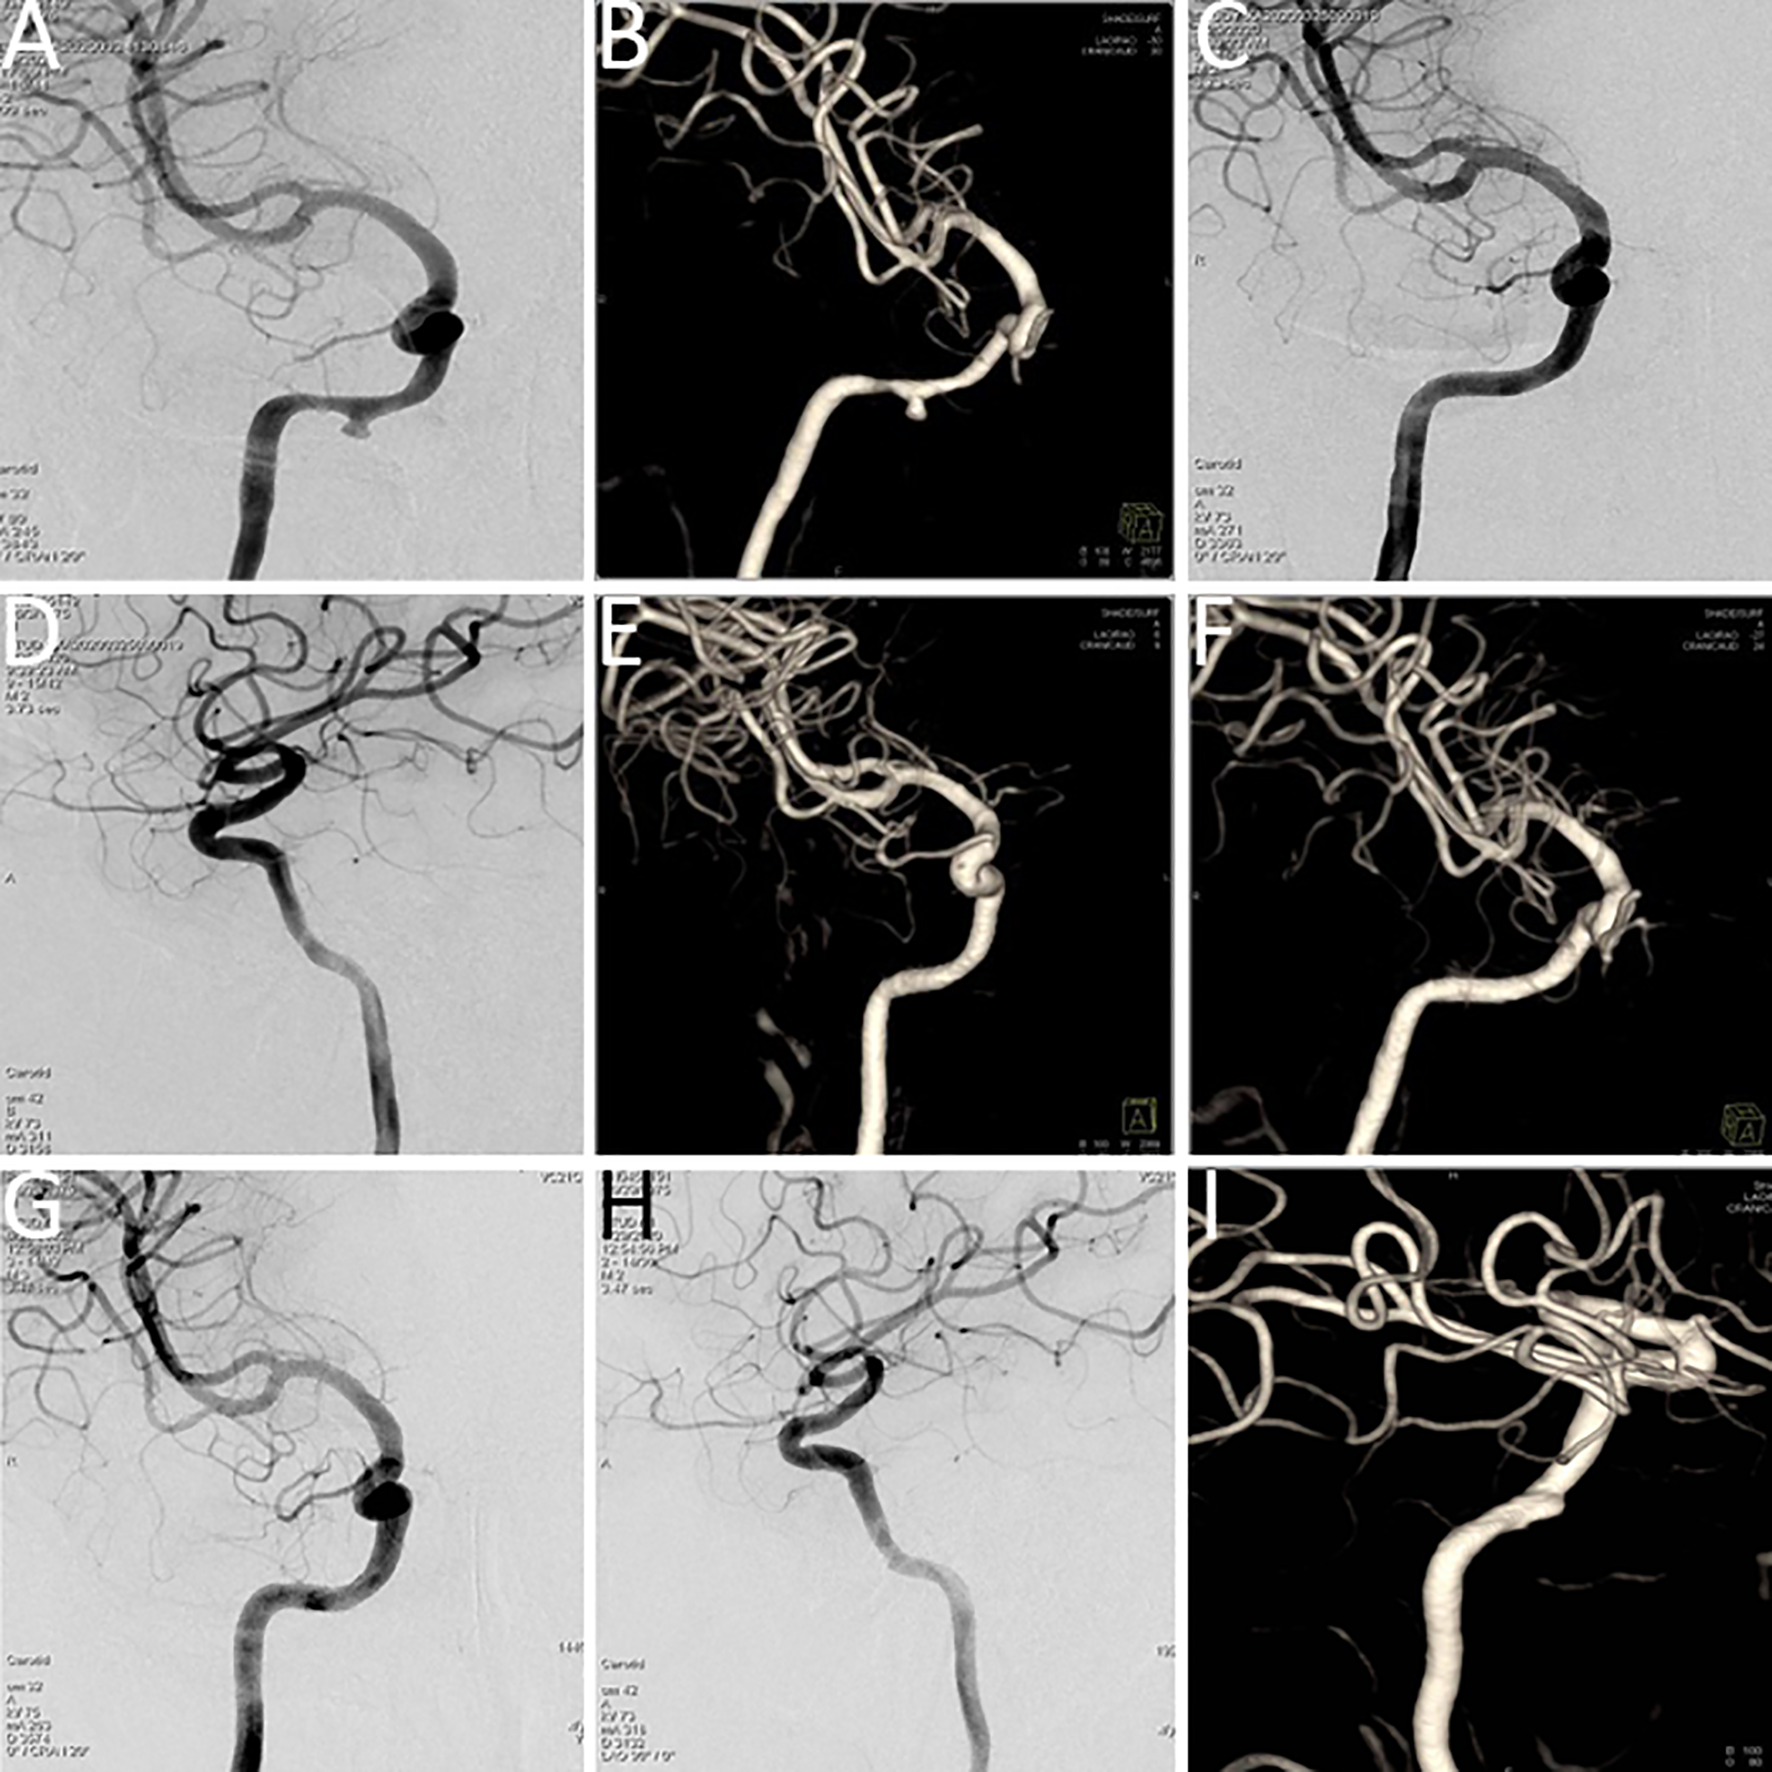

Upon admission, routine blood analysis indicated a hemoglobin level of 11.2 g/dL, raising suspicion of ICA rupture-associated hemorrhage. An urgent DSA examination confirmed the presence of a pseudoaneurysm in the petrous segment of the right ICA, with tumor-associated stenosis of the involved arterial segment. A subsequent BOT yielded a positive result (refer to Figures 3A, B).

Figure 3

(A, B) Digital subtraction angiography (DSA) indicated a pseudoaneurysm in the petrous segment of the right internal carotid artery, with tumor-related narrowing; the balloon occlusion test was positive. (C, D) Post–covered stent implantation DSA showed disappearance of the pseudoaneurysm, restoration of normal vascular morphology, and adequate perfusion of intracranial branch arteries. (E, F) Vascular reconstruction after stent implantation confirmed favorable vascular morphology and intracranial branch perfusion. (G, H) Follow-up DSA indicated recurrence of a small aneurysm distal to the stent in the petrous segment (C2) of the right internal carotid artery. (I) Vascular reconstruction angiography at three months post-stent implantation demonstrated a dissecting aneurysm.

Covered stent implantation was performed at the petrous segment of the right ICA, leading to the disappearance of the pseudoaneurysm. Post-procedural imaging demonstrated satisfactory vascular morphology and adequate perfusion of all intracranial branch arteries (refer to Figures 3C–F). Immunotherapy with sintilimab, a programmed cell death protein 1 (PD-1) immune checkpoint inhibitor, was administered every three weeks.

However, severe nasal bleeding recurred three months later. DSA and vascular reconstruction revealed septal luminal irregularities in the left carotid artery, consistent with a dissecting aneurysm (refer to Figures 3G–I).

A subsequent surgical procedure was undertaken, involving the creation of a vascular anastomosis from the right external carotid artery to the middle cerebral artery using a grafted radial artery. Concurrently, the cavernous and petrous segments of the right ICA were isolated. Immediate postoperative angiography confirmed patency of the bypass, with sufficient perfusion to the right middle cerebral artery and collateral supply to the ophthalmic artery. No perfusion was observed in the cervical, petrous, and cavernous segments of the right ICA (refer to Figures 4A, B).